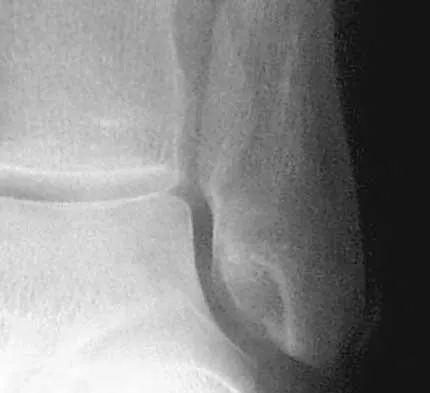

A 28-year-old man has had a 2-year history of progressive lateral ankle pain. History reveals that he underwent a triple arthrodesis at age 13 for a tarsal coalition. The pain has been refractory to braces, custom inserts, and nonsteroidal anti-inflammatory drugs. Weight-bearing radiographs of the ankle and foot are shown in Figures 3a through 3d. Surgical management should include which of the following?